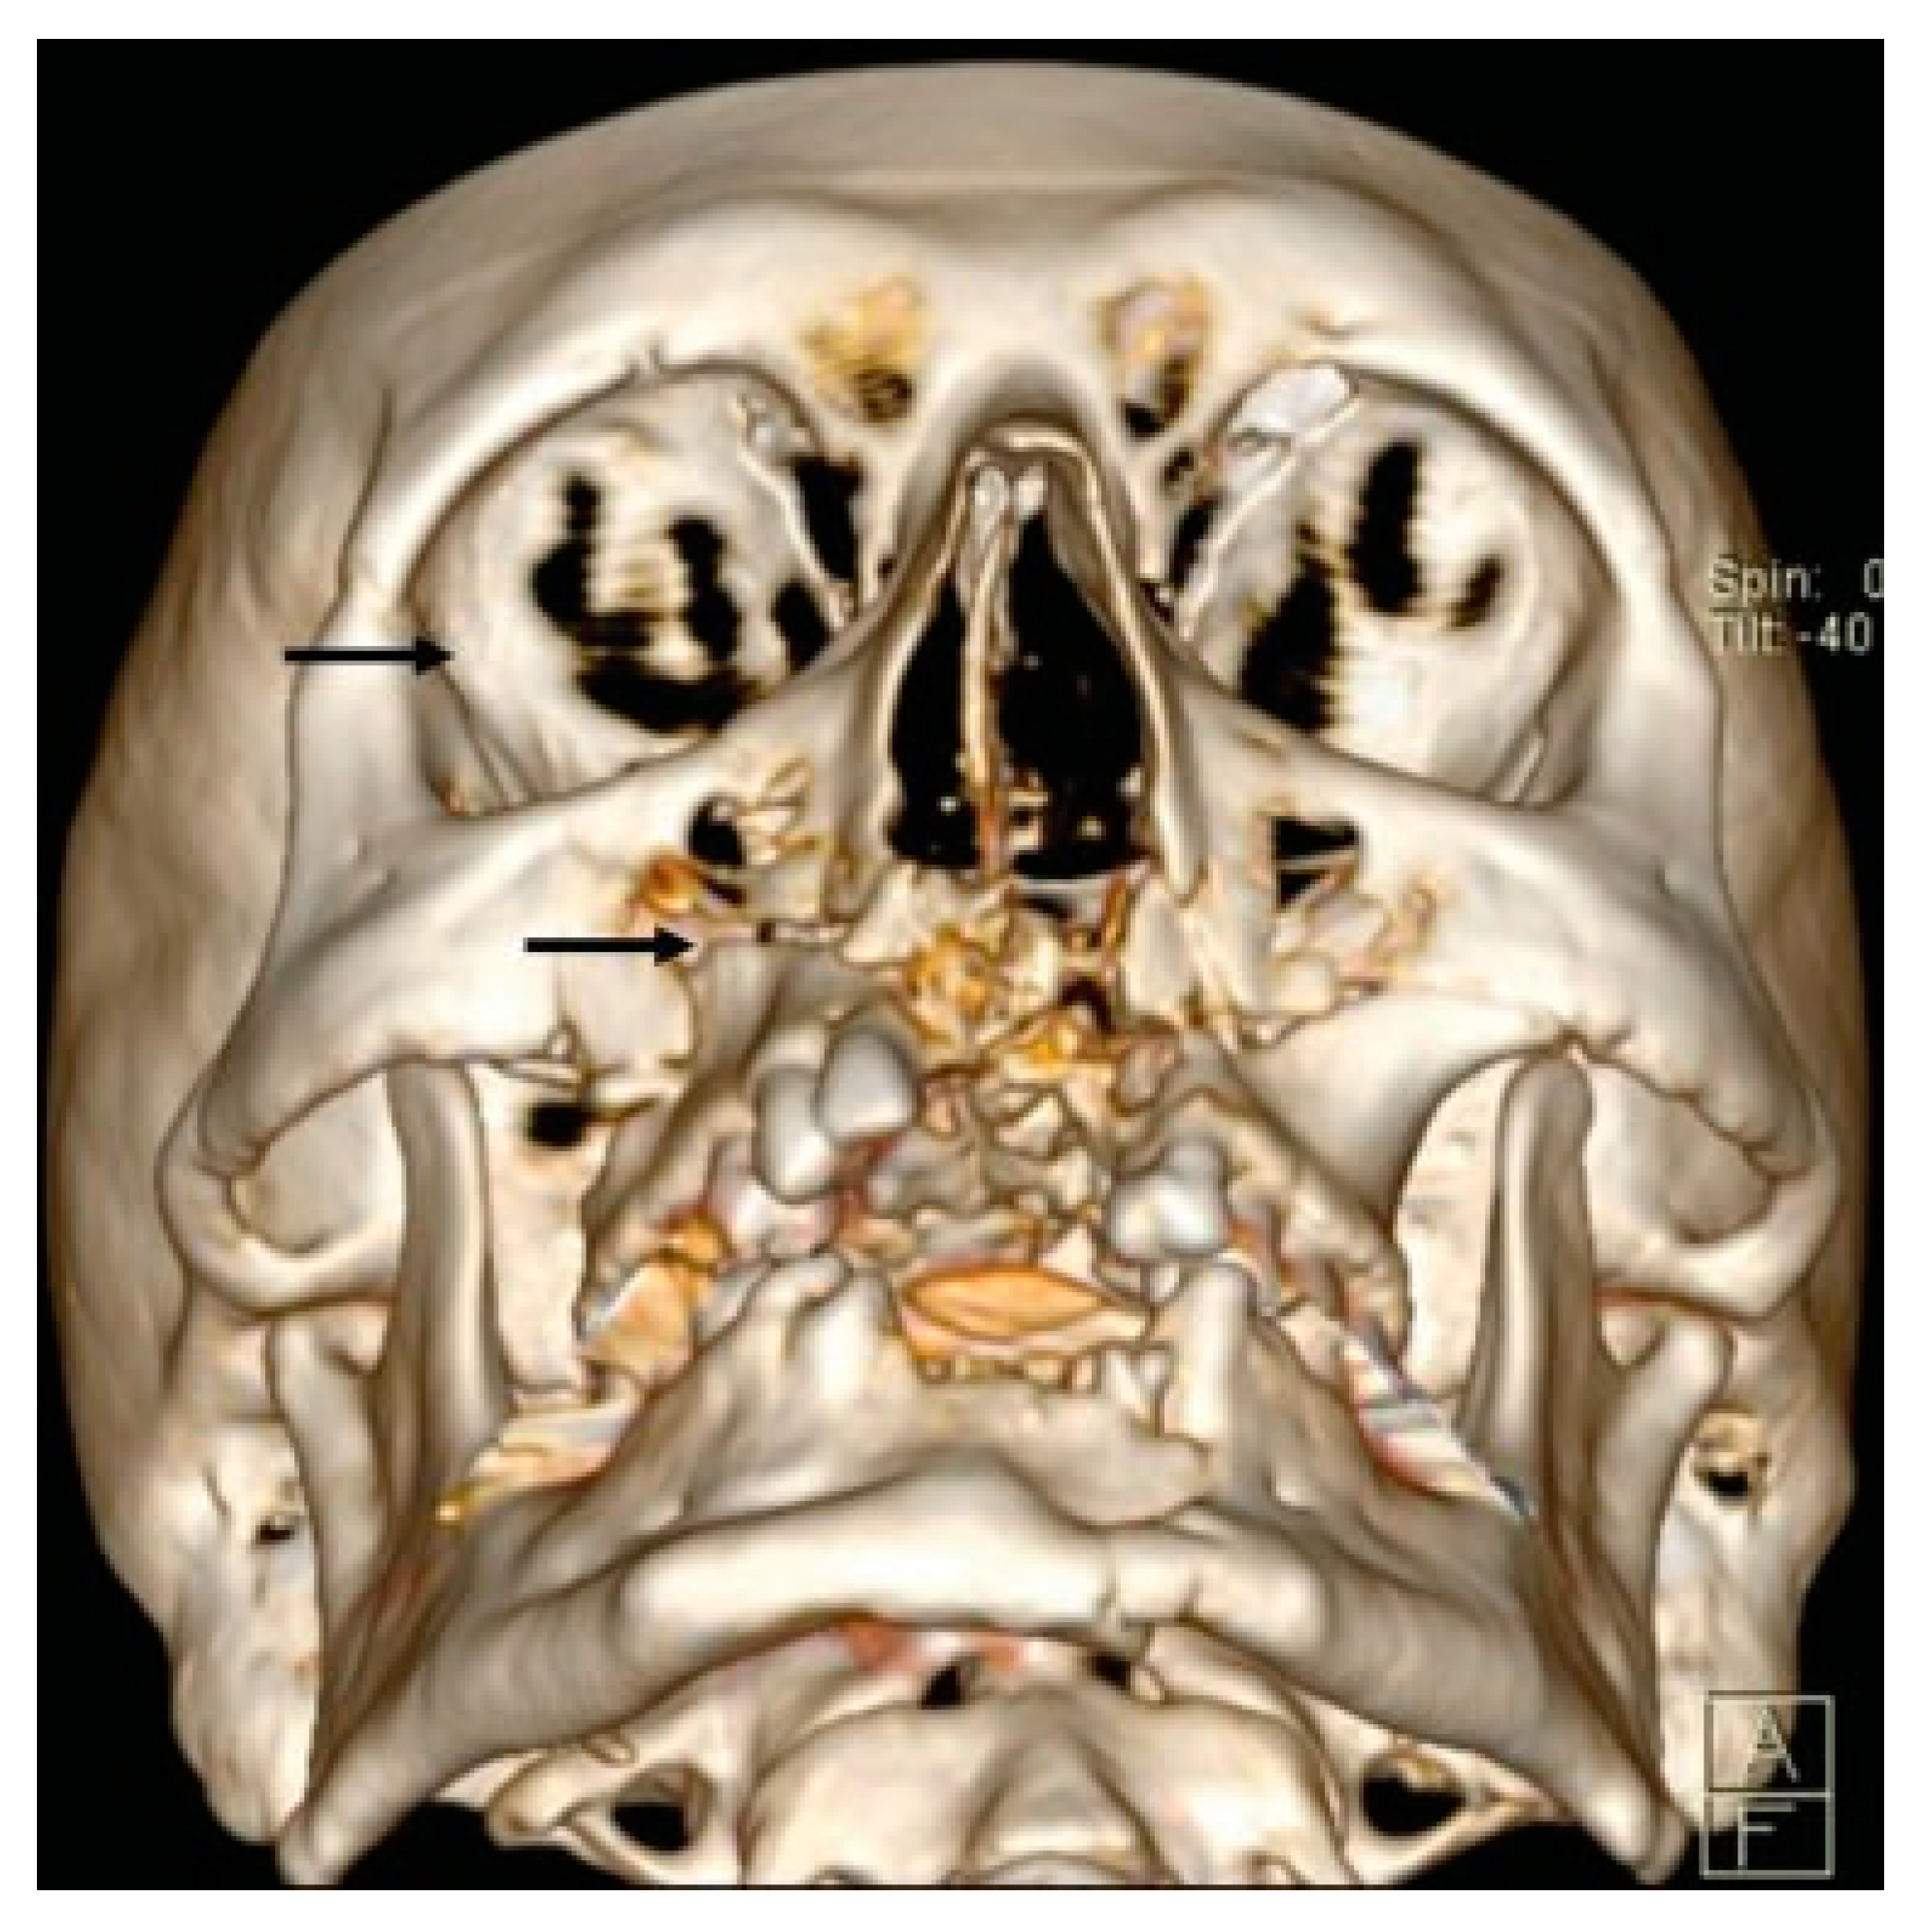

- Additional line extending from the pyriform aperture to the infraorbital rim of the same side (60%).

- Additional line extending from the infraorbital rim to the Le Fort fracture line.

- Additional line extending from the pyriform aperture to the lateral wall of orbit, without breaking the infraorbital rim of the same side (5.4%).

- Additional line extending from the infraorbital rim through the canine fossa to terminate as a fractured dentoalveolar segment of the same side, involving the fractured segment (10.9%).

- Pterygoid plates are not fractured (23.6%).

- D1: Additional Line Extending from the Pyriform Aperture to the Infraorbital Rim of the Same Side (34.5%)

- D2: Additional Line Extending from Infraorbital Rim to the Le Fort Fracture Line (25.4%)

- D3: Additional Line Extending from Pyriform Fossa to Lateral Wall of Orbit, without the Fracture of the Infraorbital Rim of the Same Side (5.4%)

- D4: Additional Line Running from the Infraorbital Rim through the Canine Fossa to Terminate as a Fractured Dentoalveolar Segment of the Same Side (10.9%)

- D5: Pterygoid Plates Are Not Fractured (23.6%)